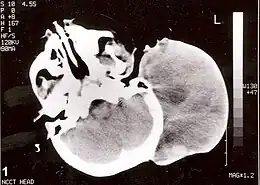

Scanner-X sans produit de contraste d'une tête montrant une large masse sans extension intracrânienne. Le diagnostic fut un rhabdomyosarcome congénital alvéolaire rétro-auriculaire.